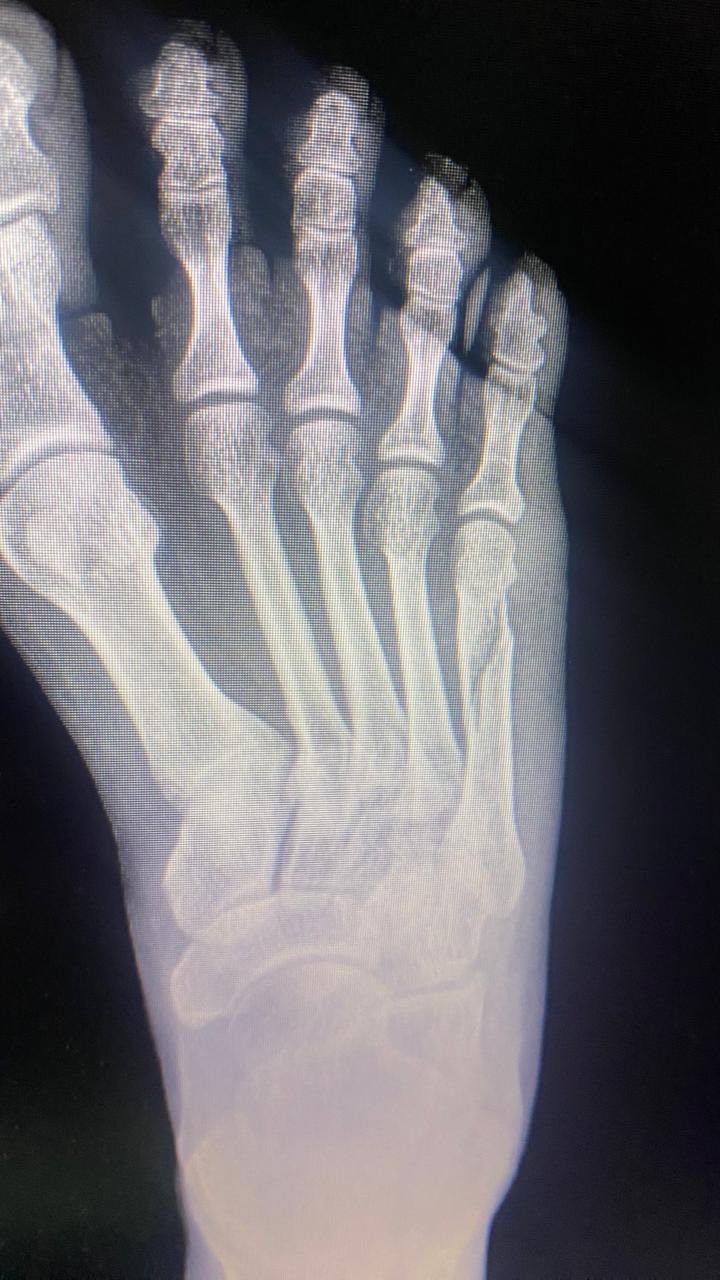

Перелом пятой плюсневой кости   1 ответ

28 августа упала на ногу, был хруст, 1 сентября пошла к врачу, оказалось перелом, наложили гипс, сняли 26 сентября, потом прописали ортез на 2 недели, ходила 2 недели в нём, мне говорят на ногу уже можно прям целиком наступать, но болит очень, вот такая ситуация на данный момент, это последний снимок уже после снятия гипса. Что можете сказать по нему?